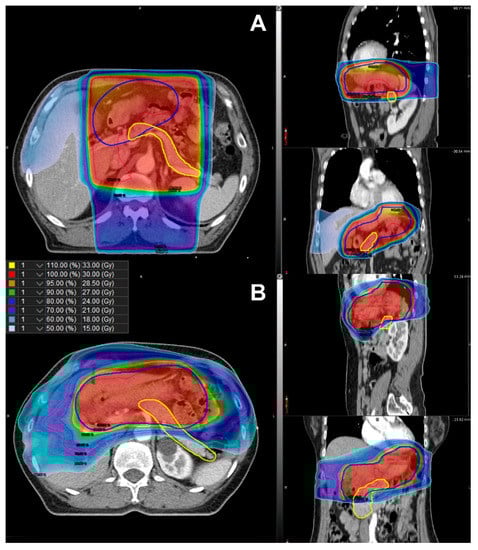

Further, RPA stratified the patients according to their risk of developing DM (Figure 2). Among the clinical factors and dosimetric parameters, patients were initially split between Dmean < 21.0 Gy and Dmean ≥ 21.0 Gy. Representative isodose distributions for a patient with Dmean ≥ 21.0 Gy using 3D-CRT and a patient with Dmean < 21.0 Gy using IMRT are presented in Figure 3. The split groups were further divided into BMI < 25.0 kg/m2 and BMI ≥ 25.0 kg/m2. The group with Dmean ≥ 21.0 Gy and BMI < 25.0 kg/m2 was once again stratified by sex. The patients with Dmean < 21.0 Gy and BMI < 25.0 kg/m2 were defined as the low-risk group (n = 102; Figure 2). Among the patients with Dmean ≥ 21.0 Gy, those with BMI ≥ 25.0 kg/m2 or male patients with BMI <25.0 kg/m2 were defined as high-risk (n = 49; Figure 2). Those patients who were not included in either the low- or high-risk groups were defined as the intermediate-risk group (n = 74; Figure 2). The 5-year cumulative incidence of DM was 0.0% (95% CI 0.0–0.0%), 3.1% (95% CI 0.8–12.3%), and 15.6% (95% CI 7.8–31.3%) in the low-, intermediate-, and high-risk groups, respectively (Figure 4, p < 0.001). The cumulative incidence of DM in the low- and intermediate-risk groups was significantly lower than that in the high-risk group (low vs. high, p < 0.001; intermediate vs. high, p = 0.020), while the difference between the low- and intermediate-risk groups was not statistically significant (p = 0.095).

Figure 3. Comparison of isodose distribution of the planning target volume (blue line) and the pancreas (yellow line) in (A) three-dimensional conformal radiotherapy with Dmean ≥ 21.0 Gy and (B) intensity-modulated radiotherapy with Dmean < 21.0 Gy. Dmean, mean dose in gray irradiated to the whole pancreas.